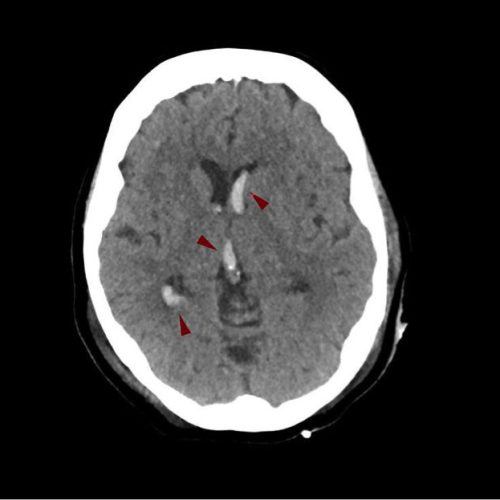

Εμφάνιση αιματώματος μέσα στο εγκεφαλικό παρέγχυμα - Ενδοκοιλιακή αιμορραγία

Εμφάνιση αιματώματος μέσα στις κοιλίες του εγκεφάλου. Εξαιτίας της ενδοκοιλιακής αιμορραγίας μπορεί να αναπτυχθεί αποφρακτική υδροκεφαλία, η οποία πολλές φορές είναι απειλητική για τη ζωή των ασθενών.